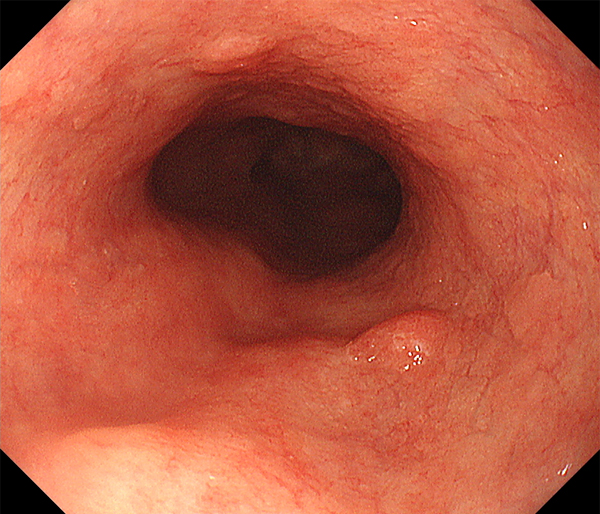

内視鏡所見と病理組織像の1対1対応が可能な症例を公募いたします。主にLSBEに発生した早期癌(HGDを含む)を対象としますが、興味深い症例であればSSBE癌でも結構です。採否は世話人へご一任ください。

症例呈示希望者は応募用紙に記入の上、代表的な内視鏡(2枚)、切除標本(新鮮、固定)、切り出し図、マッピング、代表的組織像とともに、Barrett 食道研究会事務局 barrett.shinshu@gmail.comへお申し込み下さい(10MB以下でお願い致します)。

特に、本邦では極めて稀なlong segment Barrett’s esophagus(LSBE)から発生した早期癌は、診断に難渋する場合も多く、欧米ではランダム生検による検出が標準的とされています。背景のBarrett食道もろとも全体を内視鏡切除+ラジオ波焼灼する欧米と異なり、ESDで内視鏡的な局所切除が基本の本邦では、存在診断+範囲診断(特に水平)を的確に行うことが不可欠です。

そのためには、一流の病理医による組織学的診断とエキスパート内視鏡医による拡大内視鏡像との一対一対応を徹底的に行うことで、『本来、見えないであろう拡大所見の先にある組織構築像が診えてくる』所まで内視鏡診断レベルを上げていく必要があります。その実現には、一対一対応を追究した症例(特にLSBE発生例)1例でも多く経験するしかありません。本研究会でBarrett食道腺癌(LSBE発生早期病変)を共に学び、拡大内視鏡像の一歩先を診るスキルを習得しましょう!一人でも多くの皆様のご参加をお待ちしています。